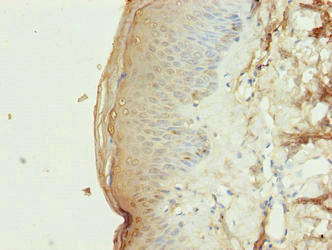

Immunohistochemistry of paraffin-embedded human skin tissue using CSB-PA839298LA01HU at dilution of 1:100